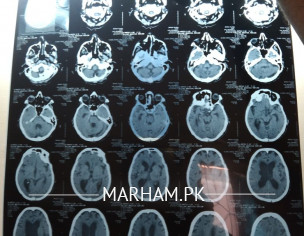

my father is under iskimic stroke for 7 swallowing,no speech,incontinuous guide about fresh CT image is attached.